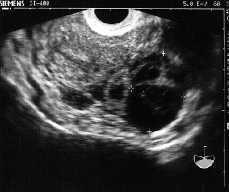

Figura 1. Imagen ecográfica de OI.

-- OI de 58 * 36 mm con imagen redondeada econegativa de 30 mm de diámetro con algún eco en su interior.

-- Diagnóstico compatible con EE en trompa derecha no accidentado en el momento del diagnóstico y OI quístico.